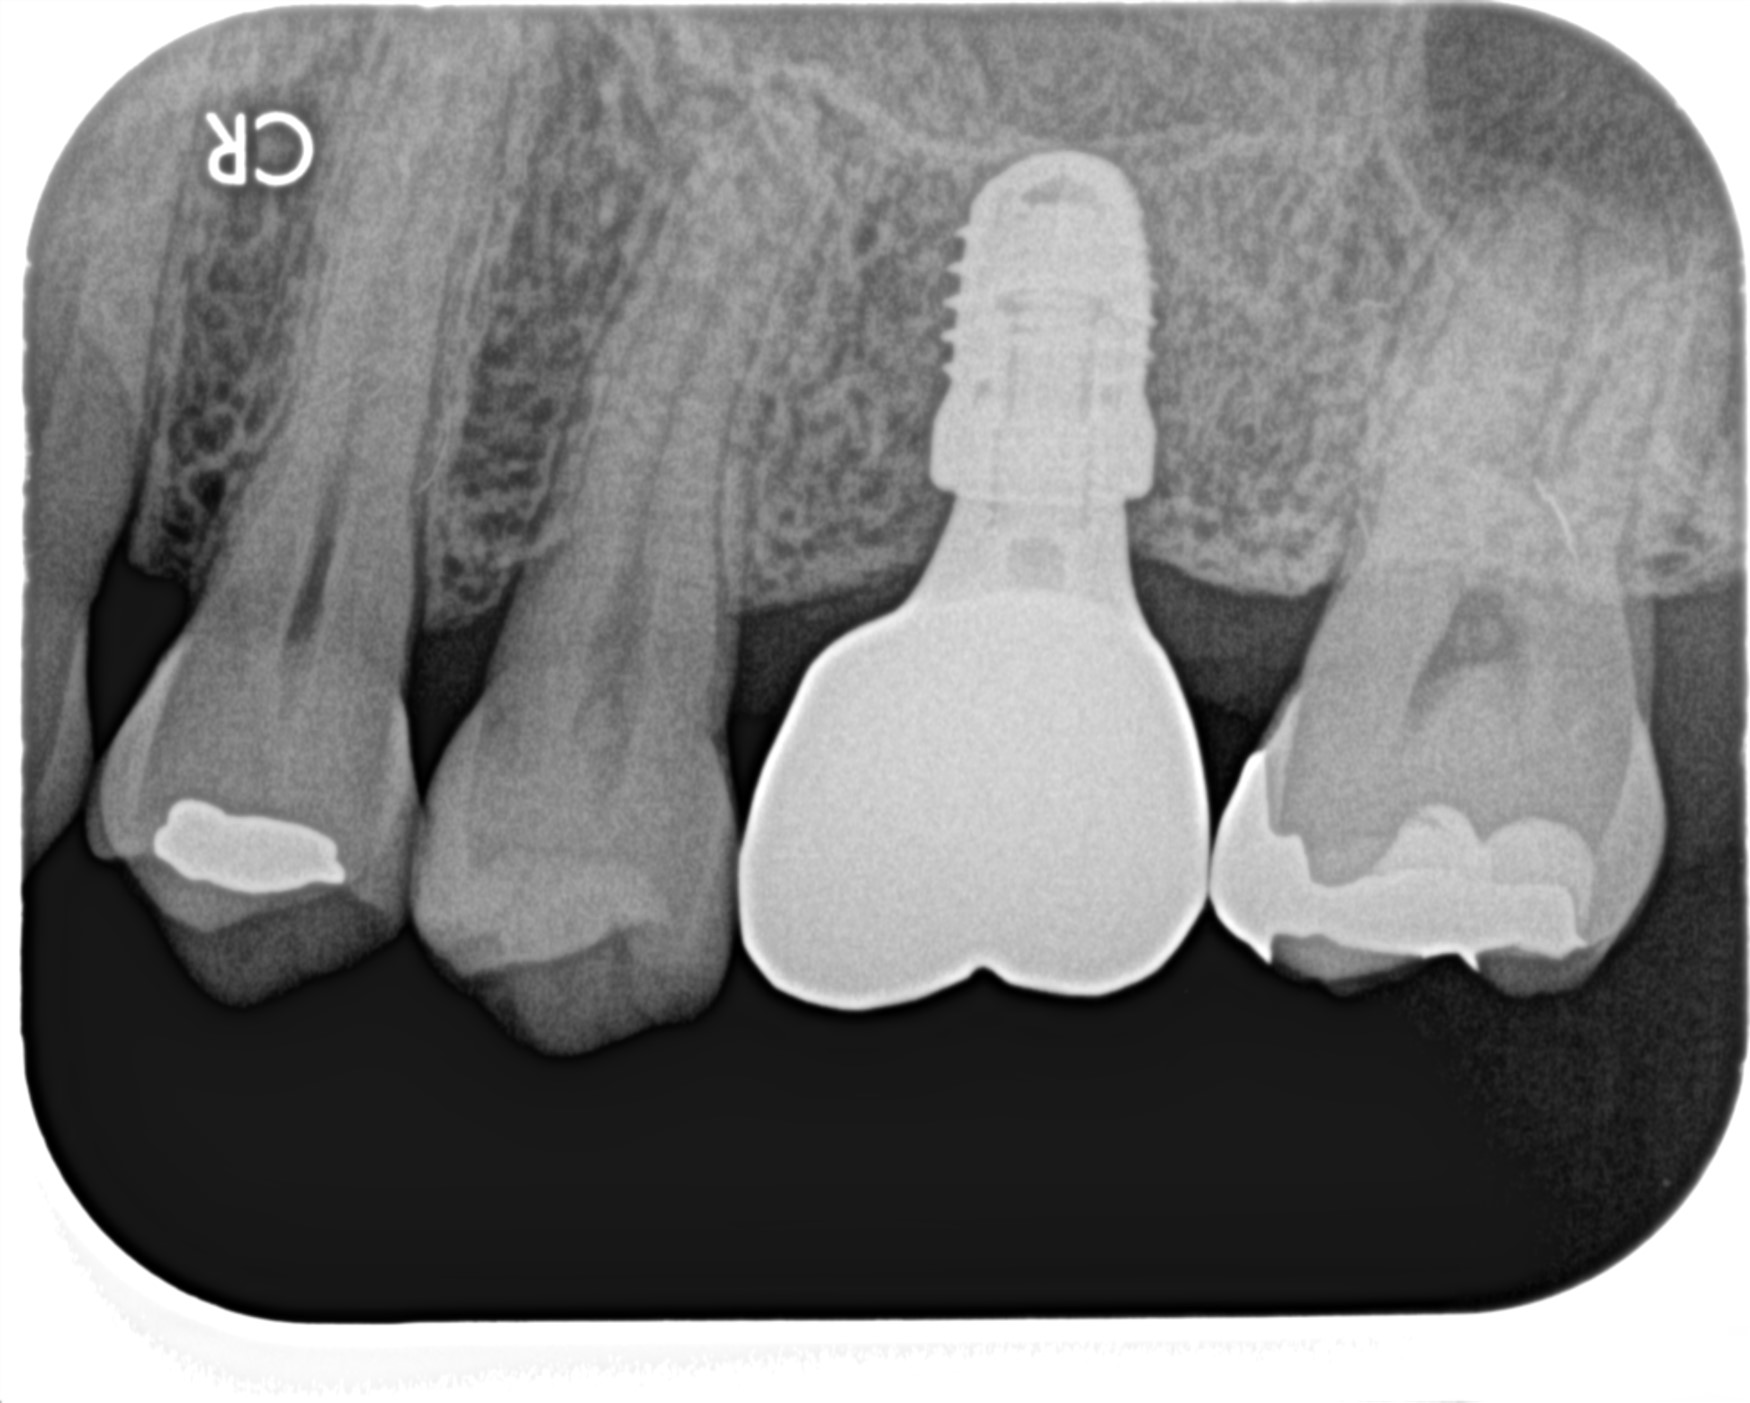

治療後